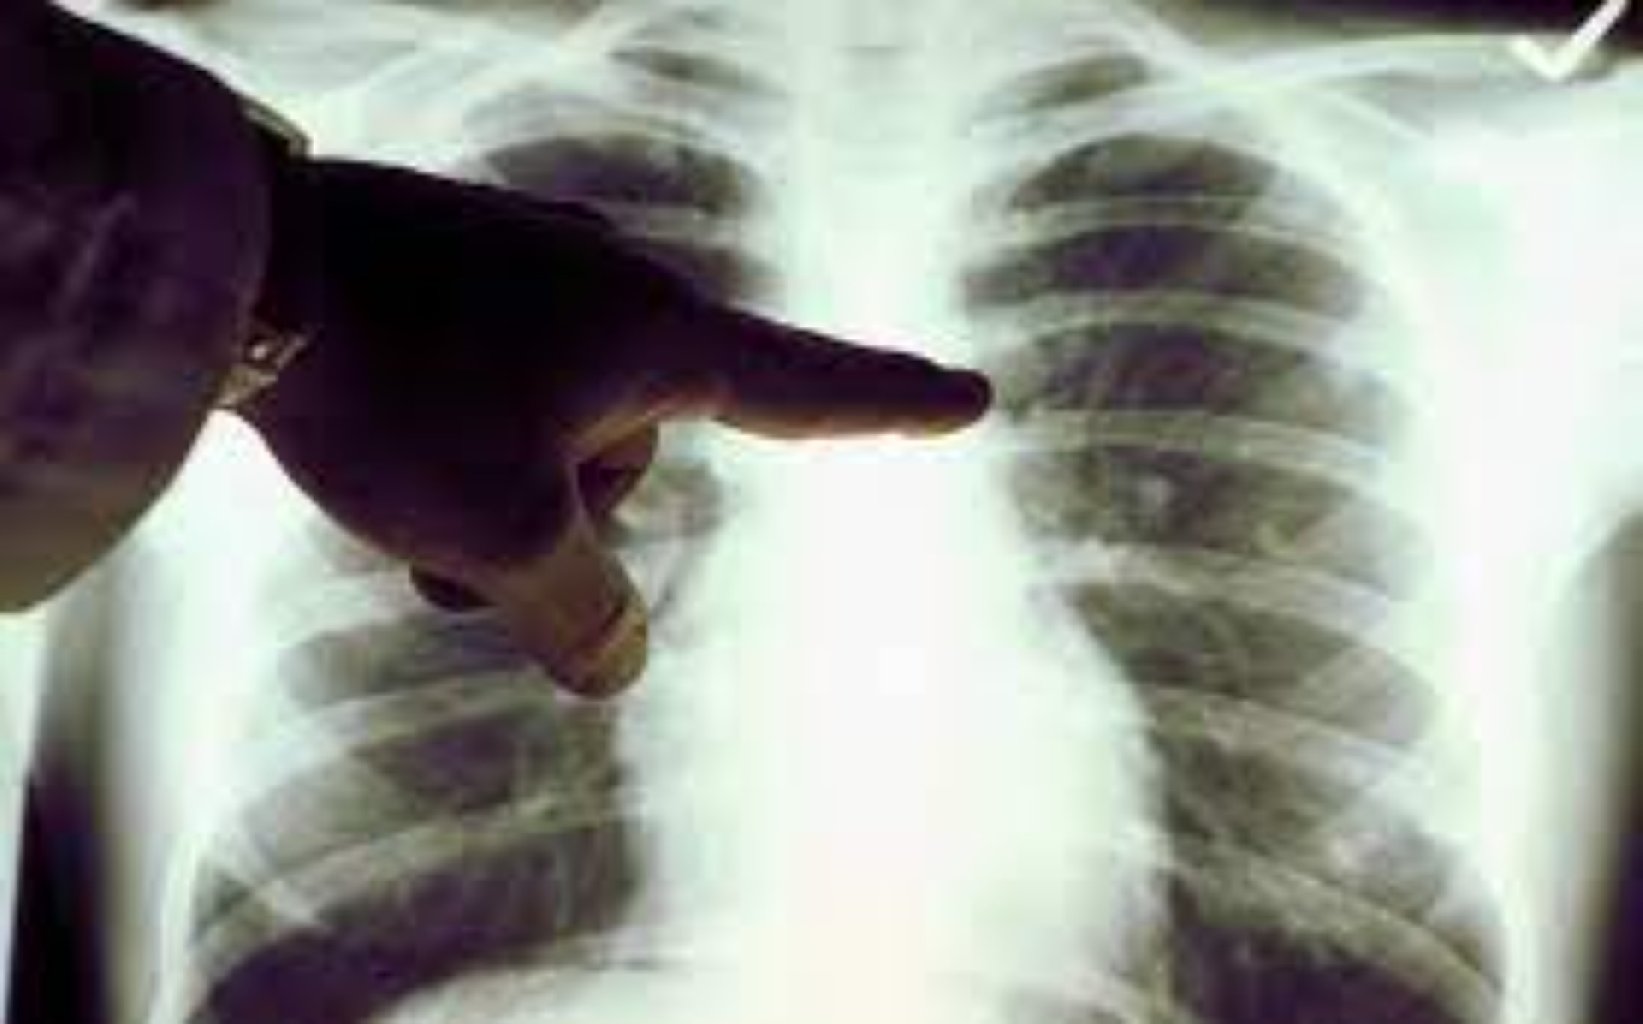

Prosedurun Məqsədi və İstifadəsi Floroskopiyada istifadə olunan rentgen şüaları, sinə qafəsinin i ...

Prosesin Amacı Ağciyər ponksiyonunun birkaç temel amacı vardır: Təşhis: Plevral efüzyonun ( ...